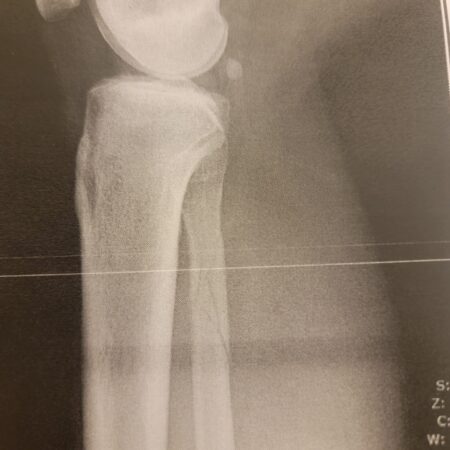

Hokkaido Ski Accident (Part 3): The surgery pain-cave

Hokkaido Ski Accident (Part 2): Meeting Dr. Tsujino

Hokkaido Ski Accident (Part 1): Breaking a bone and tearing ligaments